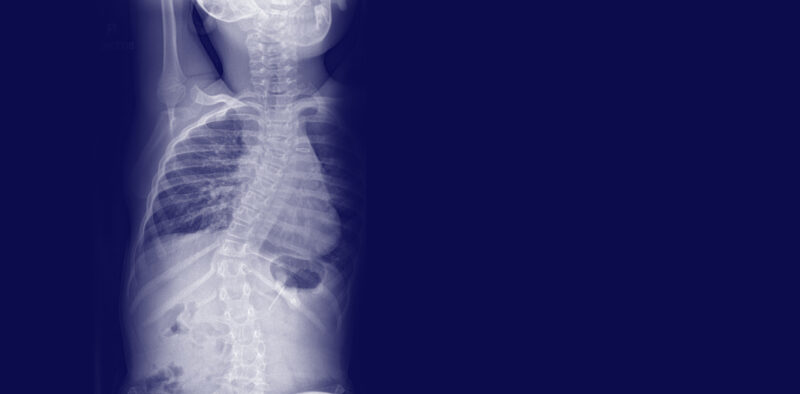

Paediatric Spine

The aims of the surgery are to stop the curve of the spine from getting worse and partly straighten the spine as much as is safely possible, to provide a good balance of the head, trunk and pelvis.